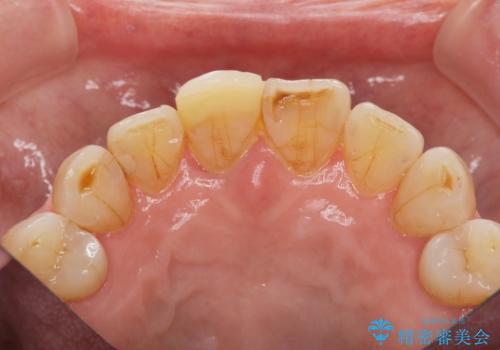

- 前歯を転倒で受傷し、審美性の回復を求めて来院されました。

近医で暫間的なコンポジットレジン修復が為されていましたが、色調に不満があるということでした。

色調の変化が少なく、長期的な予後を見込めるジルコニアクラウンで天然歯を模した審美性の回復を計画します。